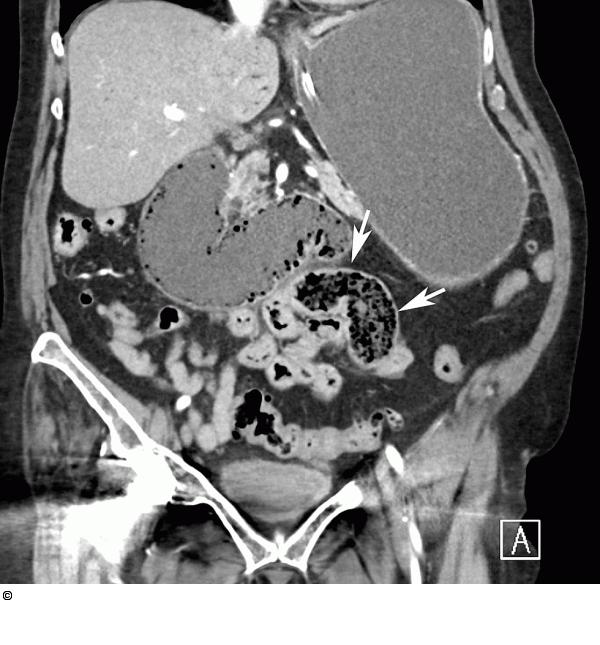

Abbildung 1b: Dünndarmschlinge Auffällig ist in einer Dünndarmschlinge eine tubuläre Struktur, die solide imponiert (Pfeile). Die distal davon gelegenen Dünndarmschlingen sind kollabiert. |

Auffällig ist in einer Dünndarmschlinge eine tubuläre Struktur, die solide imponiert (Pfeile). Die distal davon gelegenen Dünndarmschlingen sind kollabiert. |